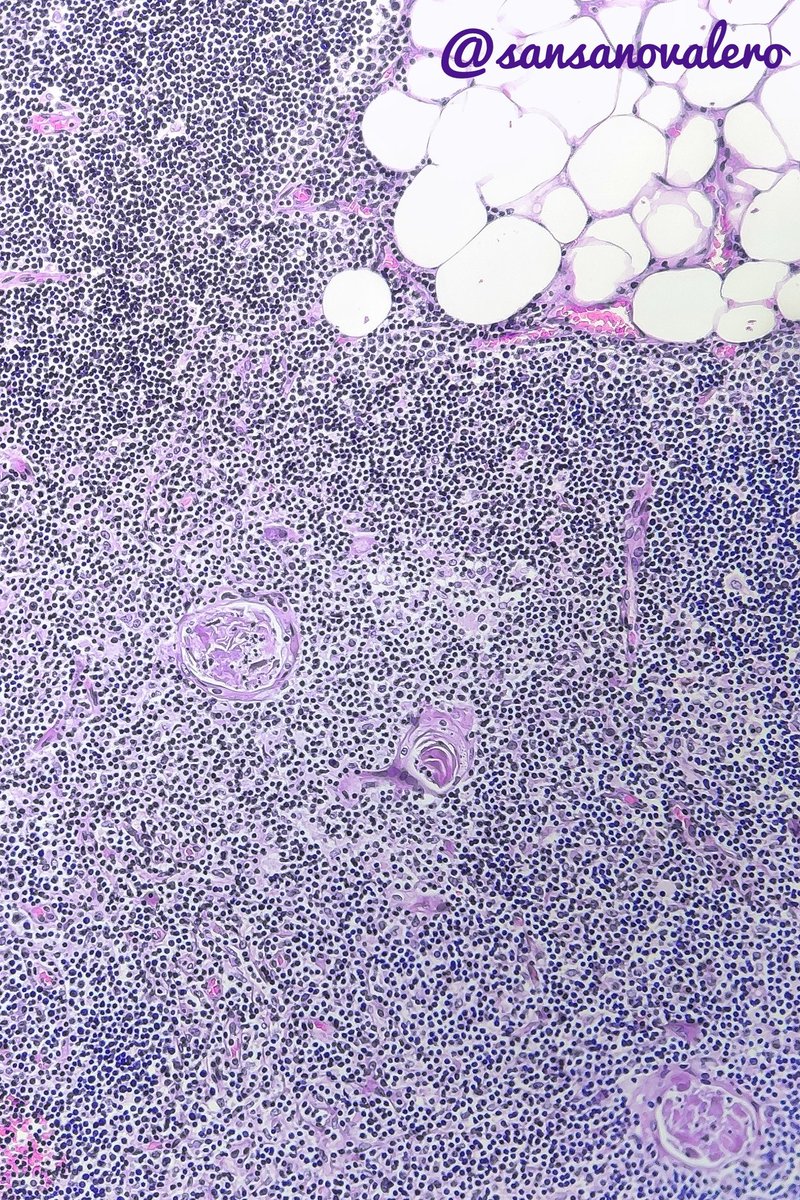

Irene Sansano, MD Phd (@sansanovalero) 's Twitter Profile Photo

True Thymic Hyperplasia in a 30 yo. Enlargement of normal thymus. Thymic cortices & medullae are well defined. Interstitial connective tissue is delicate with fat cells #pulmpath